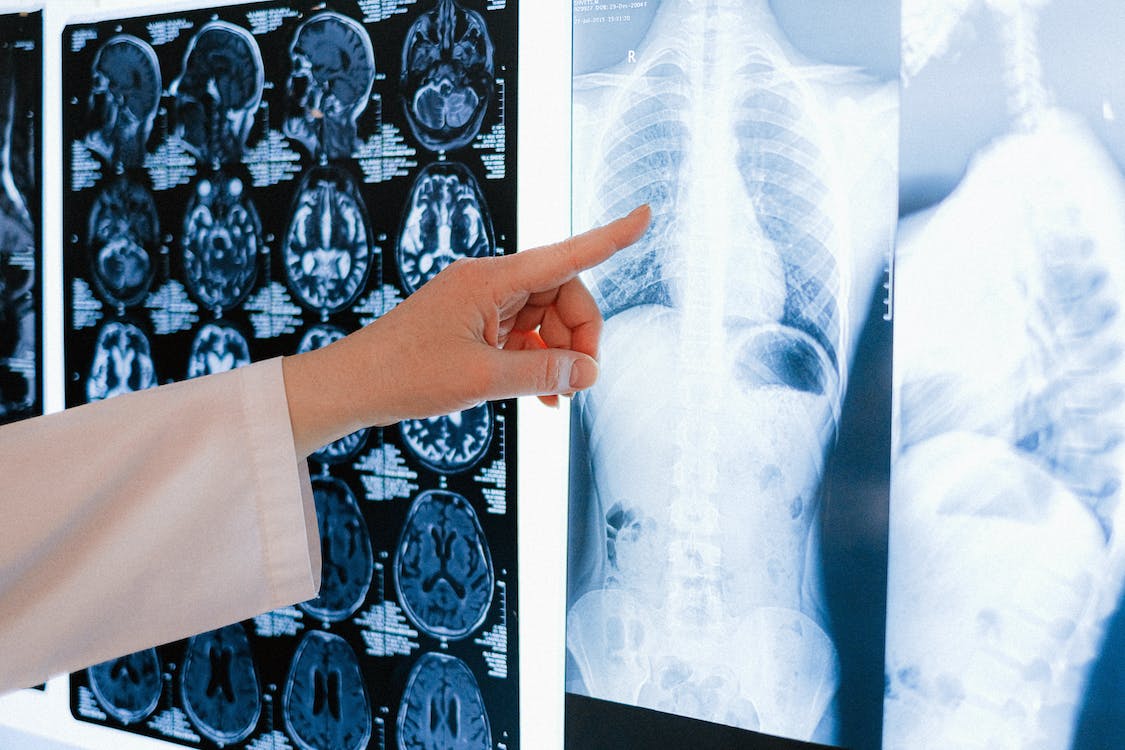

Centro de Radiodiagnóstico, con el equipo más potente del Principado de Asturias.